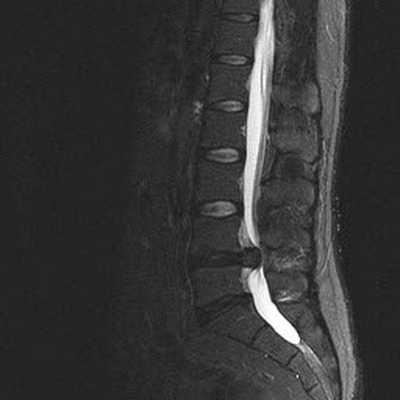

Снимок МРТ поясничного отдела позвоночника в сагиттальной проекции при остеохондрозе

Стеноз позвоночного канала поясничного отдела на снимке МРТ

Стеноз позвоночного канала поясничного отдела на снимке МРТ (Т1 взвешенное изображение)

Грыжа межпозвонкового диска и абсолютный стеноз спинномозгового канала на снимке МРТ поясничного отдела, Т2 взвешенное изображение

Снижение высоты диска, секвестрированная грыжа в области тел L4-L5 и абсолютный стеноз спинномозгового канала на МРТ снимке поясничного отдела позвоночника в сагиттальной проекции